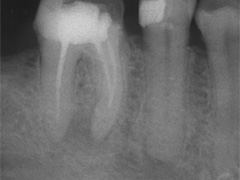

Als Zufallsbefund entdeckter, bis dahin beschwerdefreier apikaler Prozess an Zahn 36. Dessen insgesamt stark verengtes Innenraumsystem gestattete damals in erster Sitzung nur die Darstellung von 2 Kanälen. Wenn intensivstes Weitersuchen erfolglos bleibt, ist dem erfahrenen Behandler irgendwann zumindest so viel über den fehlenden Kanal bekannt: Er kann nicht sehr grosslumig sein und die Weitersuche auf den nächsten Termin zu verschieben ist nicht sehr riskant. Oft genug erlebt, gelingt dann frisch mindreseted und brainrebooted das in Sekunden, was zuvor in 20 min nicht gelingen mochte. So auch hier geschehen, bei der Suche nach dem 3. Kanal.

2 Aufnahmen sind von 2002 und die dritte vom 01.11.2010